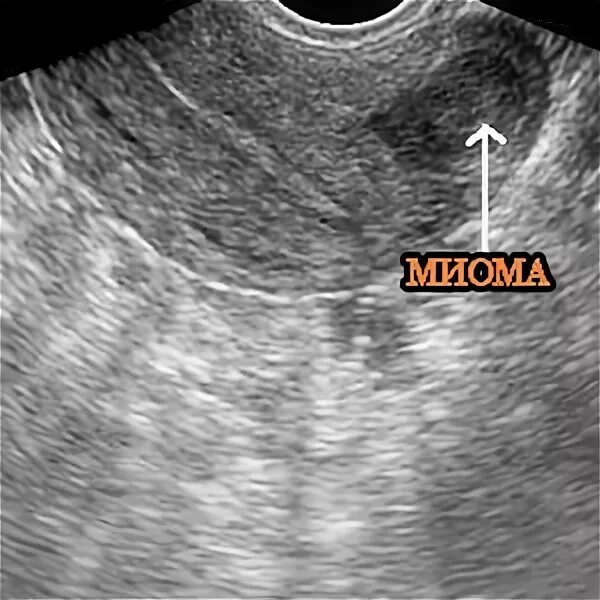

Включение в матке что это